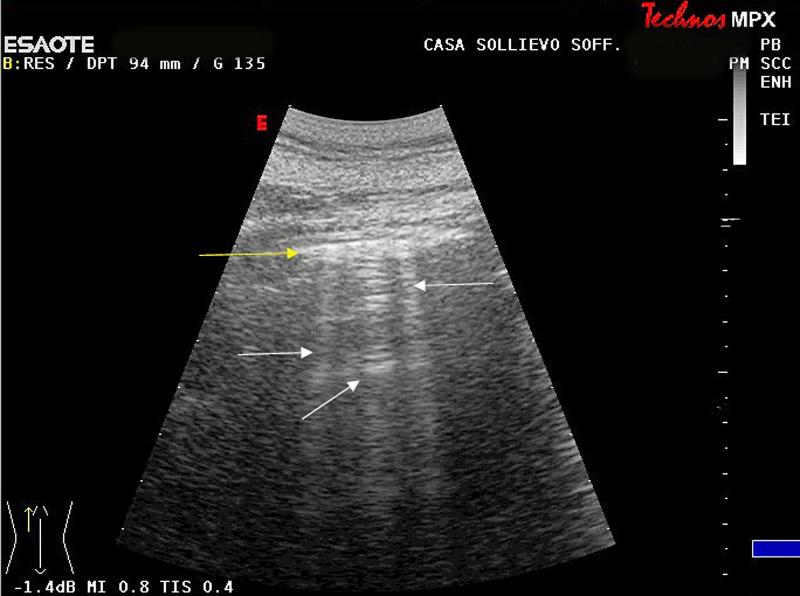

Venetian blind shadowing is a type of posterior acoustic artifact described as bands of linear shadows along lines of sight often diverging on a convex probe. Ultrasound features of adenomyosis including asymmetrical uterine wall thickening anteriorly with focal heterogeneity and associated increased blood flow as well as the venetian blind pattern of acoustic shadowing the latter may be seen with either adenomyosis or uterine fibroids. Motsa is an useful technique for the evaluation of vertebrobasilar ischemia and aneurysm scanning from the foramen magnum through the circle of willis. Rain shower 2 appearance is a sonographic finding that is typically associated with adenomyosis but can also occur in uterine fibroids the venetian blind appearance associated with adenomyosis is typically thin whereas when associated with uterine fibroids there are also edge shadows or dense posterior shadowing from calcification 1.

Ironic to its name it resembles vertical blinds rather than the classic horizontal appearance of venetian window blinds figs. The slabs typically overlap 25 40 to minimize the venetian blind artifact venetian blind artifact due to minimal saturation effects. Venetian blind shadowing is a type of posterior acoustic artifact described as bands of linear shadows along lines of sight often diverging on a convex probe 1.